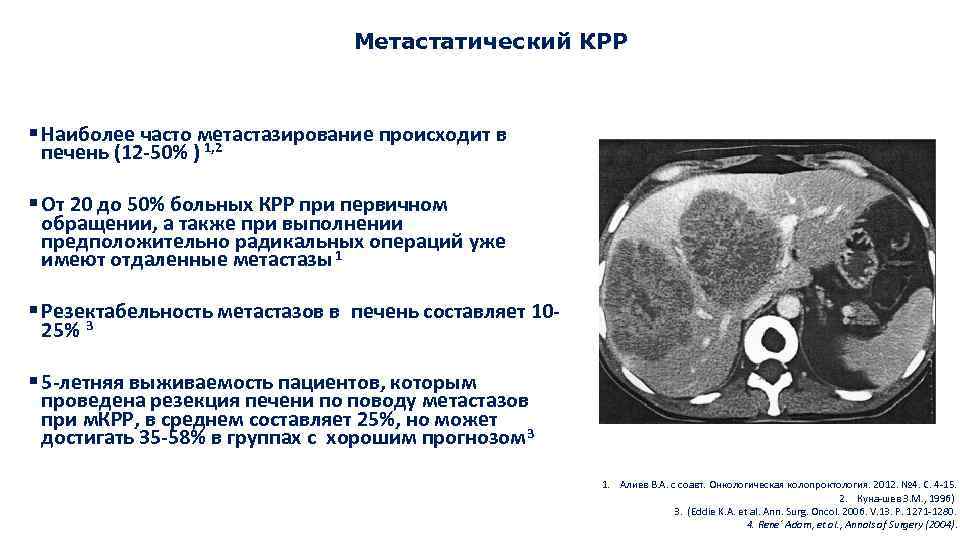

Метастатические поражения печени в ультразвуковом изображении характеризуются